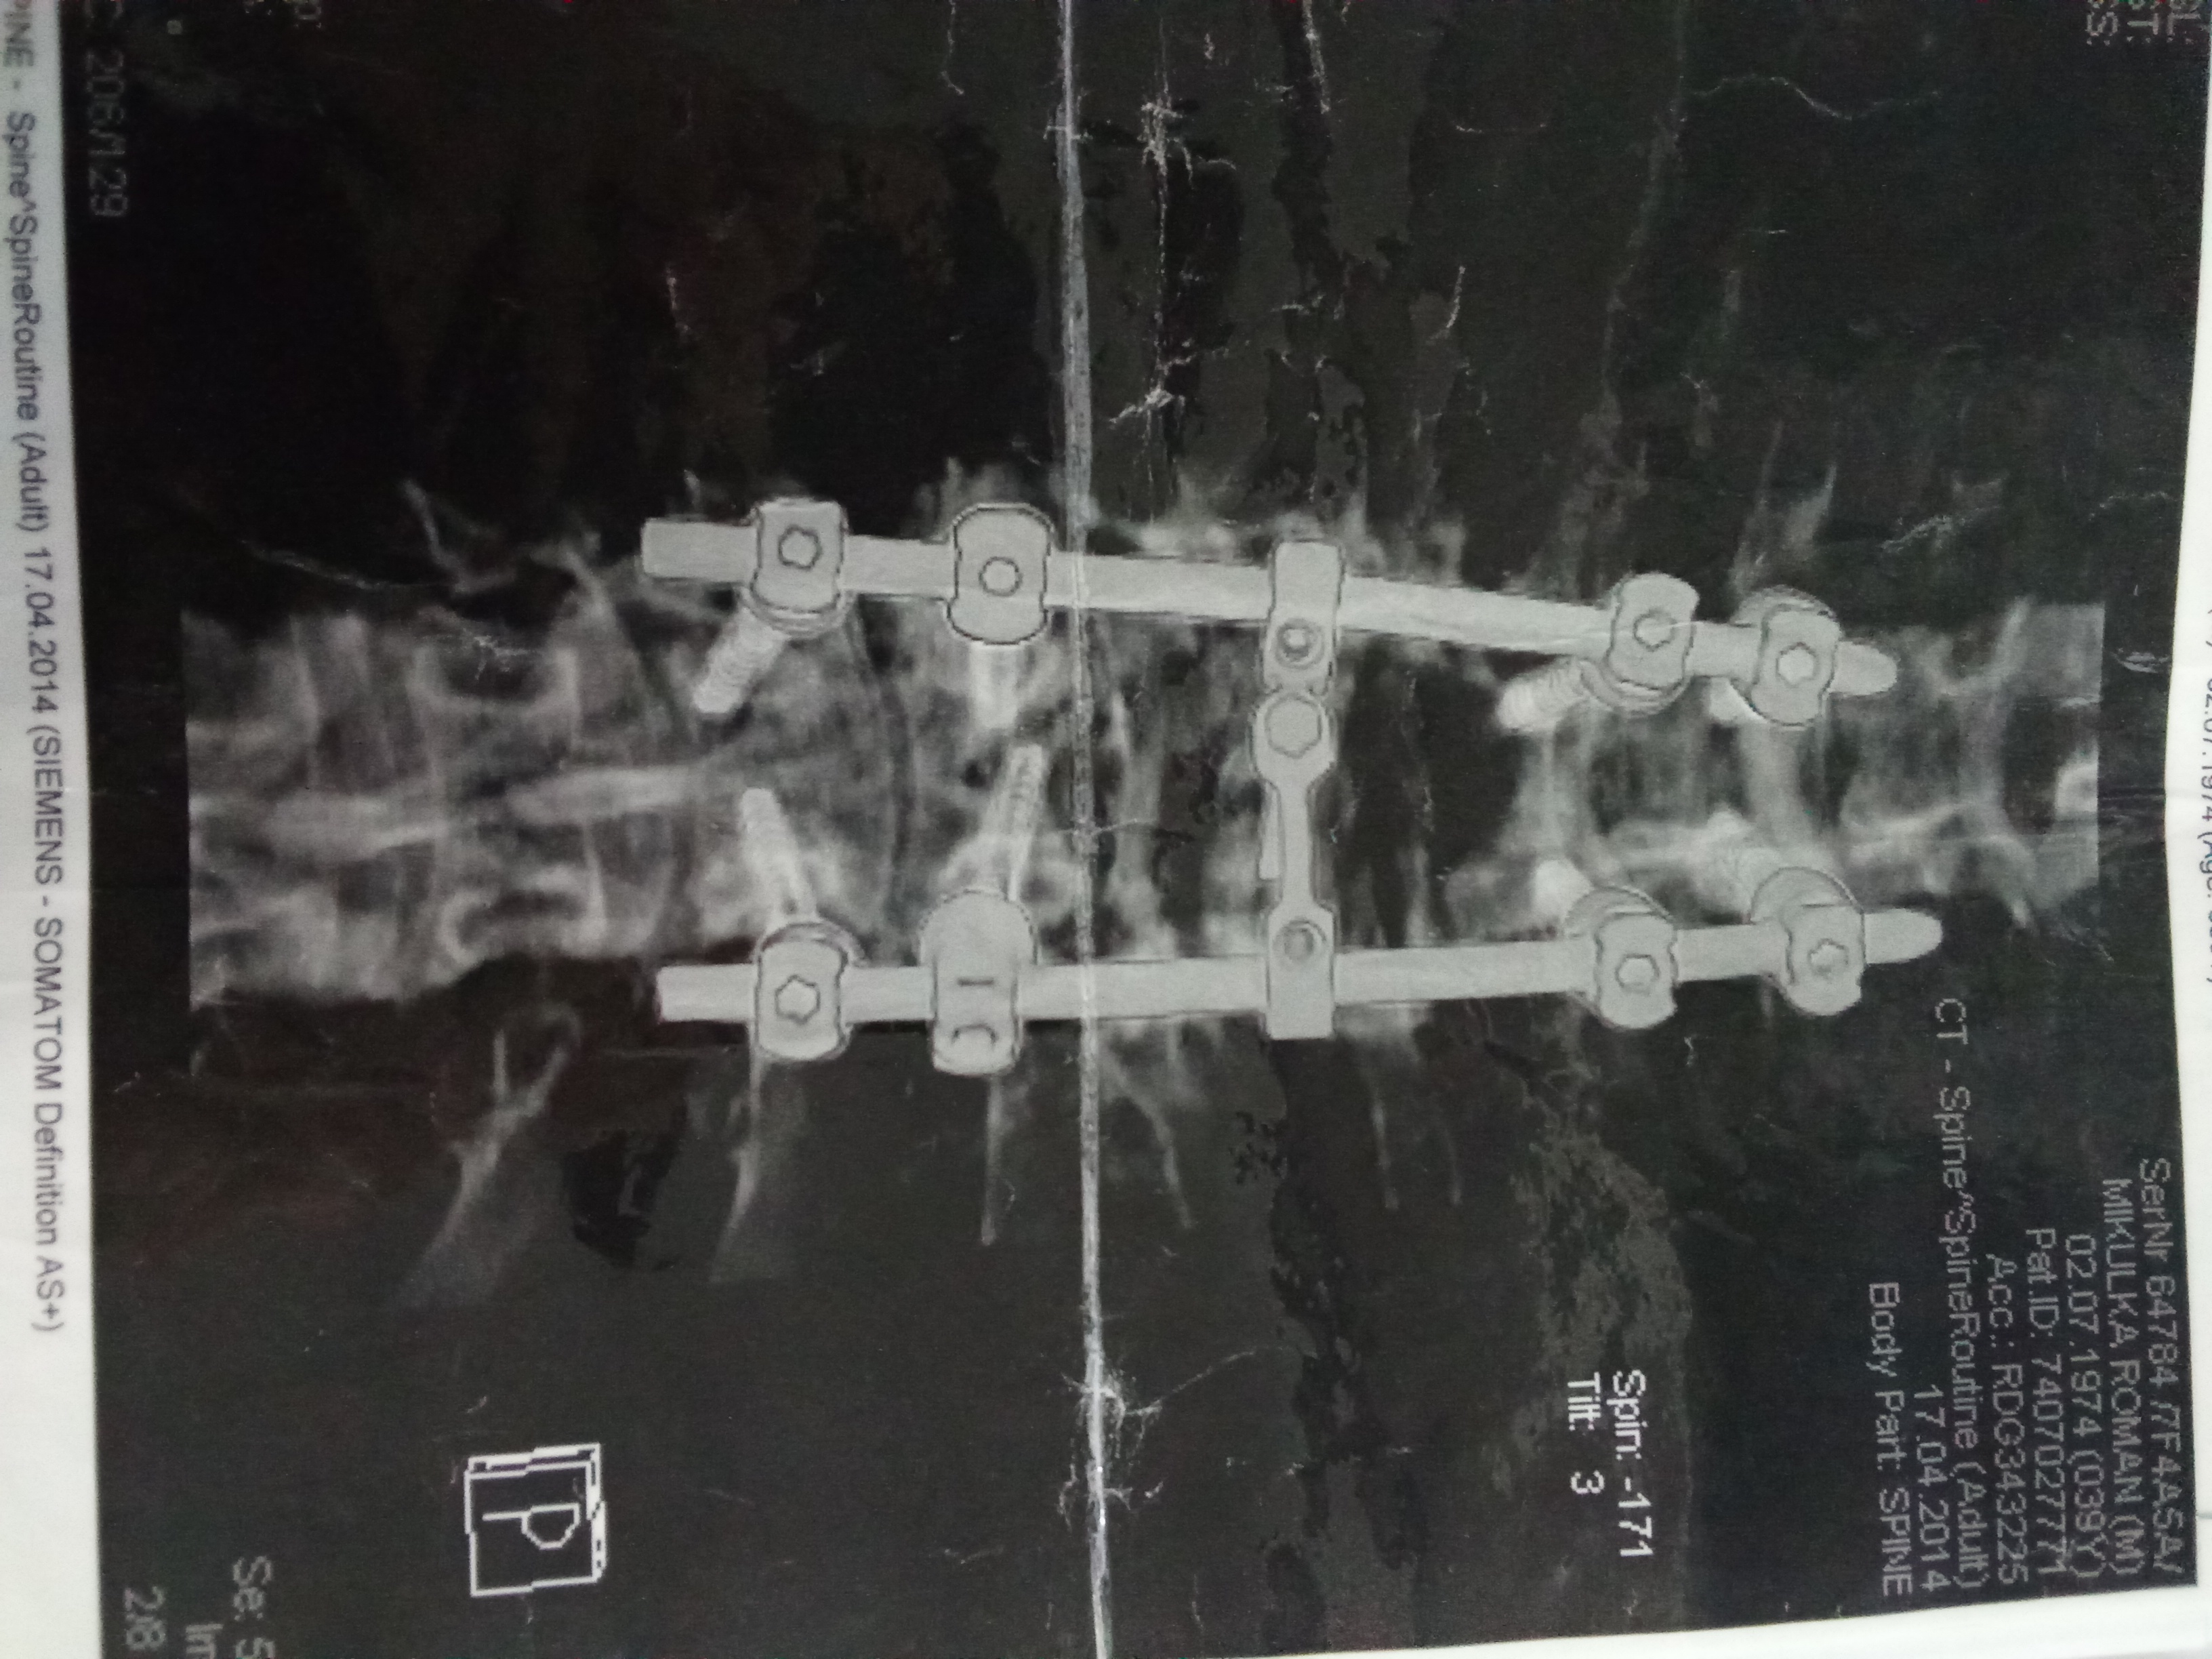

Ocino mal pred 11 rokmi úraz, spadol zo stavby, kde pracoval, spadol z veľkej výšky, kde si poradil chrbticu, miechu a je ochrnutý od pŕs nadol. Mal aj operácie chrbtice, kde mu ju šrôbami pospájali. Je odkázaný na celodennú opateru, cievkuje sa, stolicu ma iba s čìpkom, momentálne je vyše roka iba na posteli kôli veľkému dekubitu na zadku.